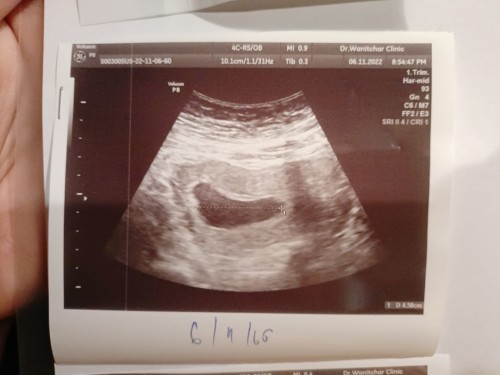

ประจำเดือนขาด 2เดือน ภาพอัลตร้าซาวด์แบบนี้ถ้ารอพอจะมีโอกาสเจอน้องไหมคะ

ที่ ปจดขาดไปอาจจะไข่ตกช้าก็ได้ค่ะ ครรภ์ยังอ่อน